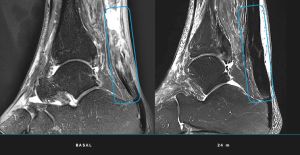

- Regeneració total: Les ressonàncies magnètiques van confirmar que tots els pacients van assolir la regeneració completa del tendó al final del seguiment de 24 mesos.